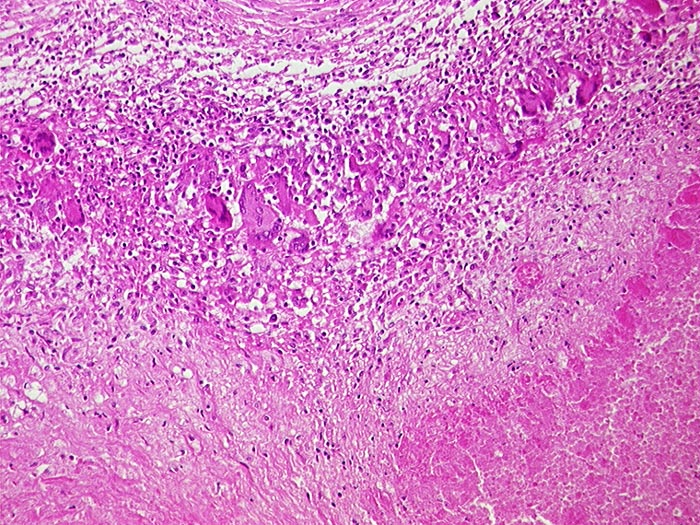

Atypische Mykobakteriose

Entzündung infektiös

Lymphknoten, abdominal

Mesenteriale Lymphknoten mit verkäsenden Granulomen aus Epitheloidzellen und Riesenzellen.

Nachweis von Mycobacterium avium intracellulare

AIDS. HIV Positivität bekannt seit 2 Jahren bei iv Drogenabusus. Pneumocystis carinii Pneumonie.